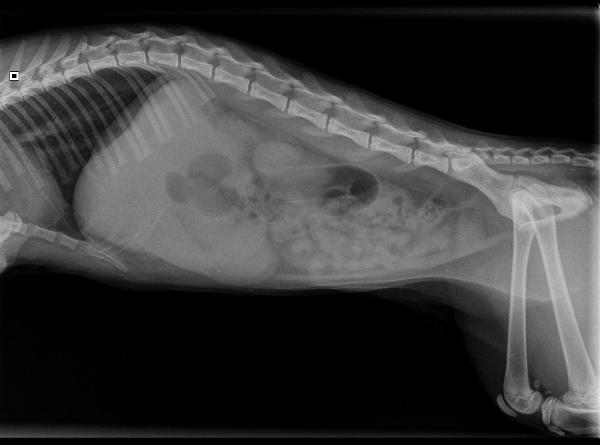

De volgende dag is Balou eerder zieker dan beter geworden. Het braken is dan wel gestopt, maar de buikpijn is verergerd. We besluiten een röntgenfoto te maken om meer informatie te krijgen over de oorzaak. Op de röntgenfoto zijn we vooral een erg onrustige darm. De hele darm is leeg en er zijn gebieden waar veel gas zichtbaar is. Bij het klinisch onderzoek denken we iets hards te voelen in de buik, maar goed voelen valt bij zo'n gespannen buikje nog wel eens tegen.

Omdat we het geenszins vertrouwen hebben we besloten om in de buik van Balou te gaan kijken en dat was geen overbodige luxe: halverwege de darm zit een stuk samengeperste ballon klem. Het stuk kan niet meer voor- of achteruit. We hebben dit stuk ballon operatief uit de darm moeten verwijderen en nu we toch in de buik zaten hebben we Balou direct gesteriliseerd. Dat was dan wel weer een geluk bij een ongeluk. De volgende dag was Balou al weer helemaal opgeknapt en een stuk fitter. Van de eigenaar hoorden we dat Balou de dag daarna weer helemaal als nieuw was. Gelukkig!

Balou's buik op de röntgenfoto